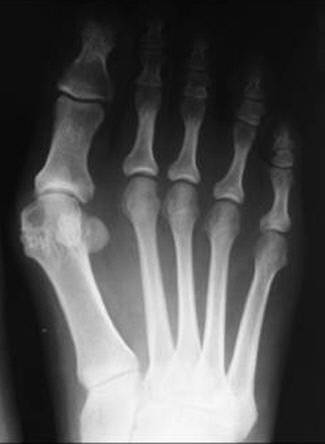

엄지발가락인 무지가 새끼발가락 쪽으로 휘는 무지외반증이 심해지면 돌출되는 엄지 관절 부위가 신발과 반복적으로 마찰하면서 통증과 염증을 유발한다. 대체로 평발이거나 발볼이 넓은 경우, 볼이 좁고 굽이 높은 신발을 자주 신는 경우 무지외반증에 걸릴 위험이 커진다. 환자들에겐 통증이 심한 엄지발가락 주변부를 바닥에 딛지 않고 걸으려는 습관이 생기기 쉬운데, 이 경우 보행 자세에도 이상이 생기면서 무릎이나 허리까지 통증이 나타날 수 있다.

무지외반증은 치료하지 않고 방치하면 계속 악화되는 질환이므로 빠른 치료가 중요하다. 변형이 심하지 않은 초기에는 발가락 교정기 등을 착용해 진행을 어느 정도 막을 수 있다. 하지만 증상이 호전되지 않거나 변형과 통증이 심하다면 교정을 위한 수술이 불가피하다. 무지외반증 수술은 변형된 엄지발가락 주변으로 지나가는 중요한 신경과 인대, 혈관 등의 조직 손상을 피해야 하므로 난도가 높다. 하지만 최근에는 절개하는 부위를 최소한으로 줄여 뼈와 인대 손상도 줄일 수 있는 수술 기법들이 나와 있어 과거보다 부담이 줄었다. ‘미카(MICA)’ ‘미타(MITA)’ 교정술 등은 4~5㎜ 크기의 작은 구멍으로 수술을 진행하고 피부를 봉합할 필요가 없어 흉터는 거의 없고 회복 속도는 빠른 것이 장점이다.

윤영식 바른세상병원 수족부센터 원장은 “증상을 방치하다 무지외반각이 40도 이상의 중증 변형으로 진행될 경우 수술이 더욱 복잡해지며 이후 재발 확률도 높아질 수 있다”며 “엄지발가락은 보행에 매우 중요한 구조물이기 때문에 수술에 대한 두려움으로 치료를 미루기보다는 하루빨리 정확한 진단 후 그에 맞는 치료를 받아야 수술 후 합병증은 적고 좋은 치료 결과를 얻을 수 있다”고 말했다.